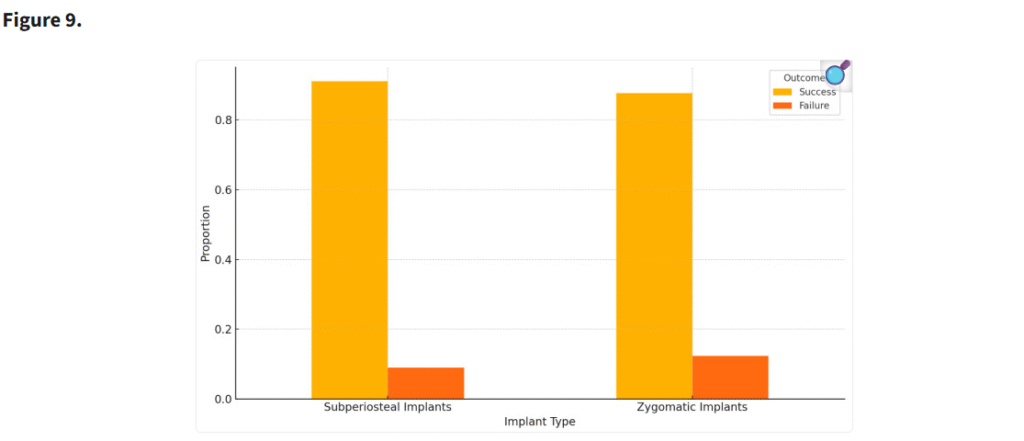

重度の上顎萎縮症例において、個別設計のインプラントはザイゴマインプラントと比較して低い失敗率を示した(Figure 8)。ザイゴマインプラントの生存率(96.3%)と骨膜下インプラントの生存率(97.1%)との間に統計学的に有意な差は認められなかったものの(p = 0.278)、骨膜下インプラントのわずかに高い生存率は、その患者固有の解剖学的形態に適合するカスタマイズ設計によるものと考えられる。この個別化アプローチにより、インプラントおよび周囲骨への応力集中が軽減され、安定性および長期的な統合が向上した(Figure 9)。

骨膜下インプラントとザイゴマインプラントの成功率および失敗率を比較した棒グラフ。p値:0.65 は、提供されたデータに基づき、両者の成功率と失敗率の間に統計学的に有意な差がないことを示している。